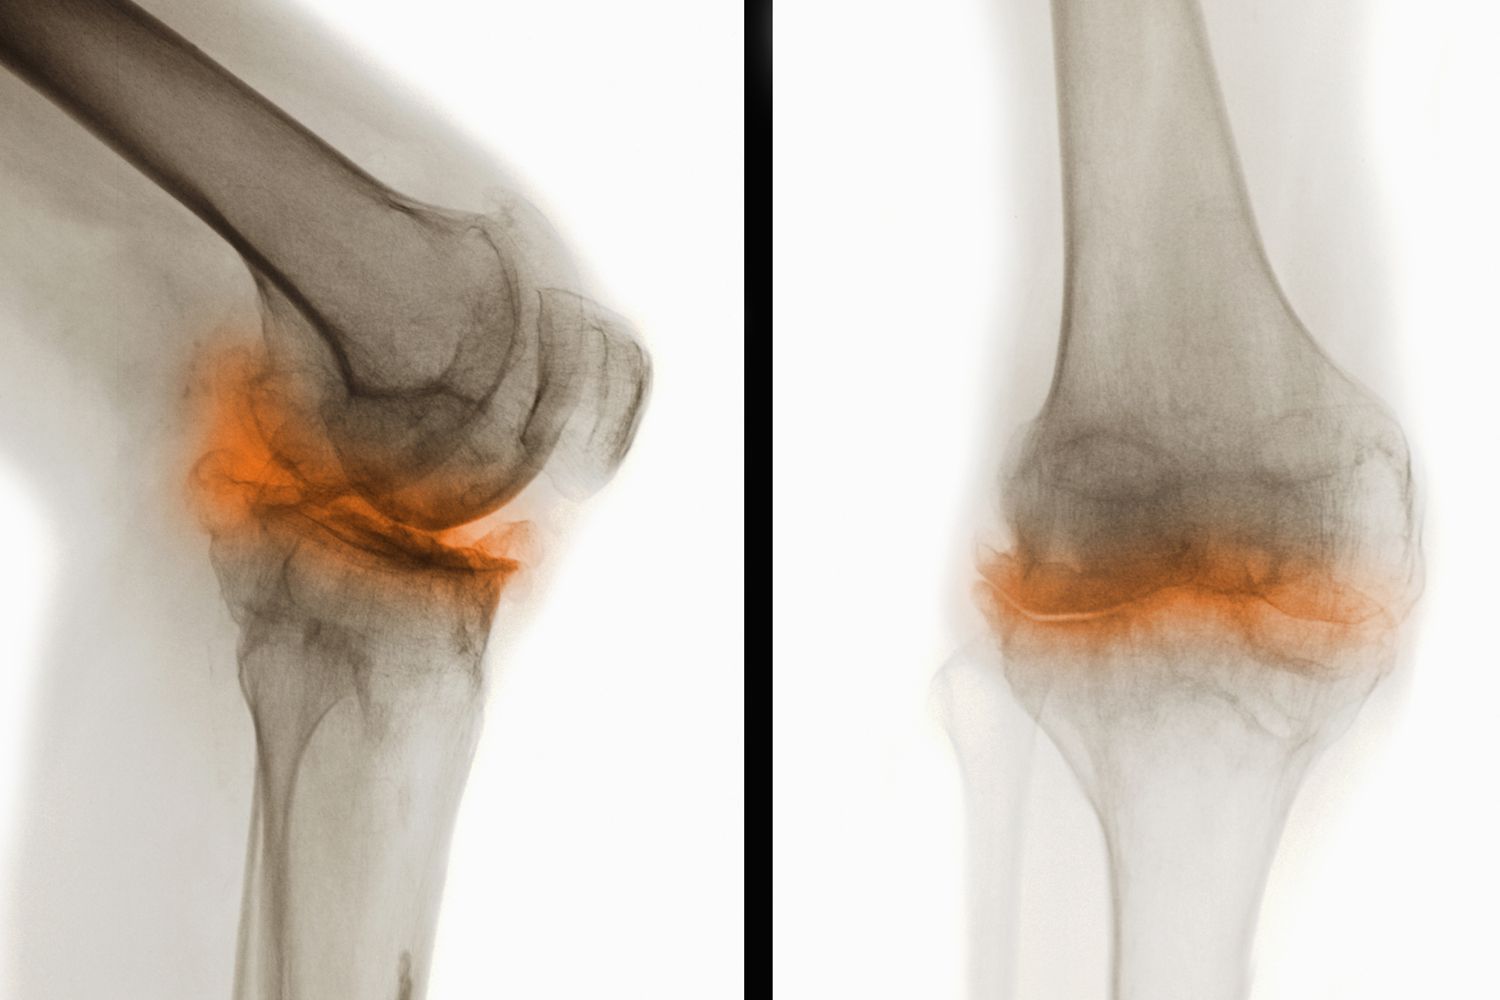

干細胞治療骨關(guān)節炎是一種新興且具有前景的治療方法。骨關(guān)節炎是一種常見(jiàn)的退行性關(guān)節疾病,主要表現為關(guān)節軟骨退化和骨質(zhì)增生,導致疼痛、僵硬和活動(dòng)受限等癥狀。干細胞治療通過(guò)利用干細胞的自我更新、多向分化和免疫調節能力,為骨關(guān)節炎患者帶來(lái)了新的希望。這也讓干細胞治療骨關(guān)節炎成為了研究的熱點(diǎn)。

骨關(guān)節炎(Osteoarthritis,簡(jiǎn)稱(chēng)OA)是一種常見(jiàn)的慢性退行性關(guān)節疾病,主要表現為關(guān)節軟骨的退化和破壞,導致關(guān)節疼痛、僵硬和功能障礙。這種疾病通常發(fā)生在中老年人群中,尤其是負重較大的膝關(guān)節、髖關(guān)節、脊柱及遠側指間關(guān)節等部位。